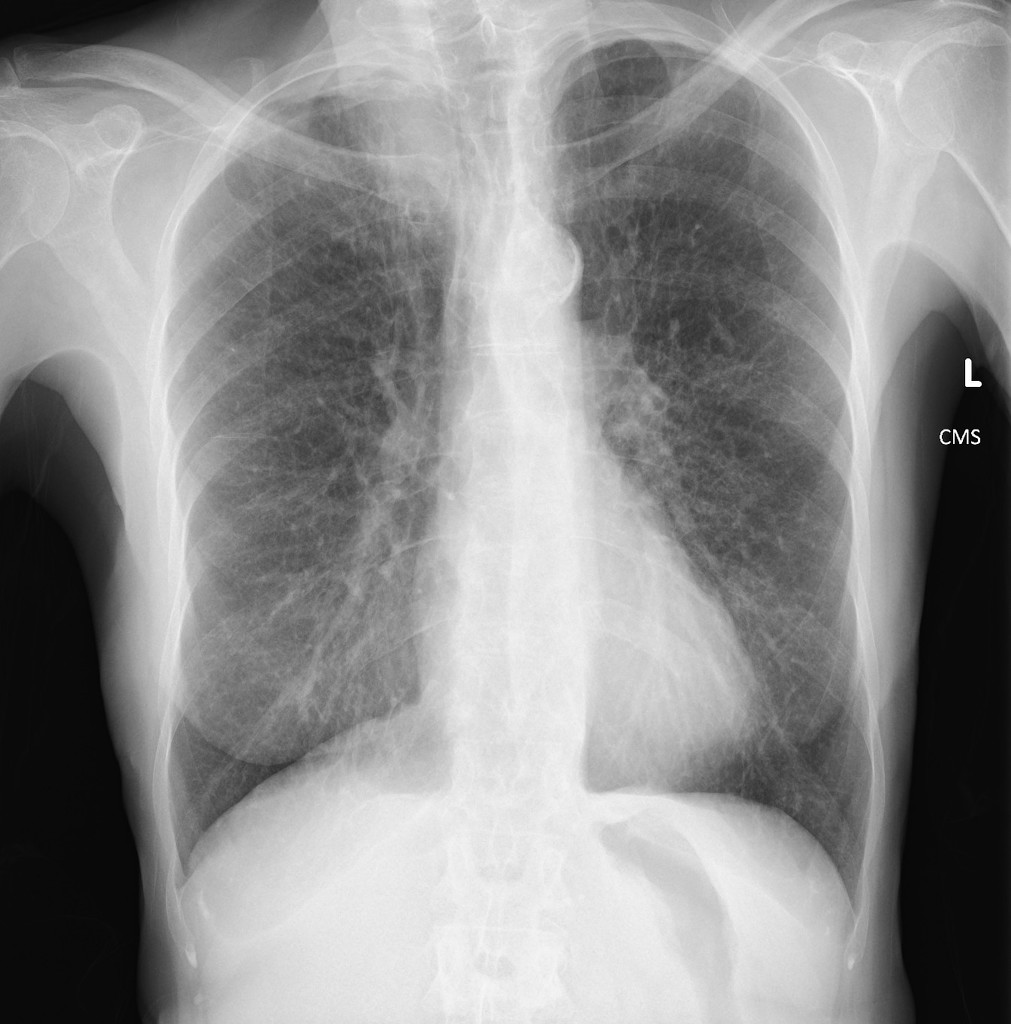

Example 2

Take a look at the following example showing consolidation. Click on the box to reveal the diagnosis.

Right sided Pancoast Tumour